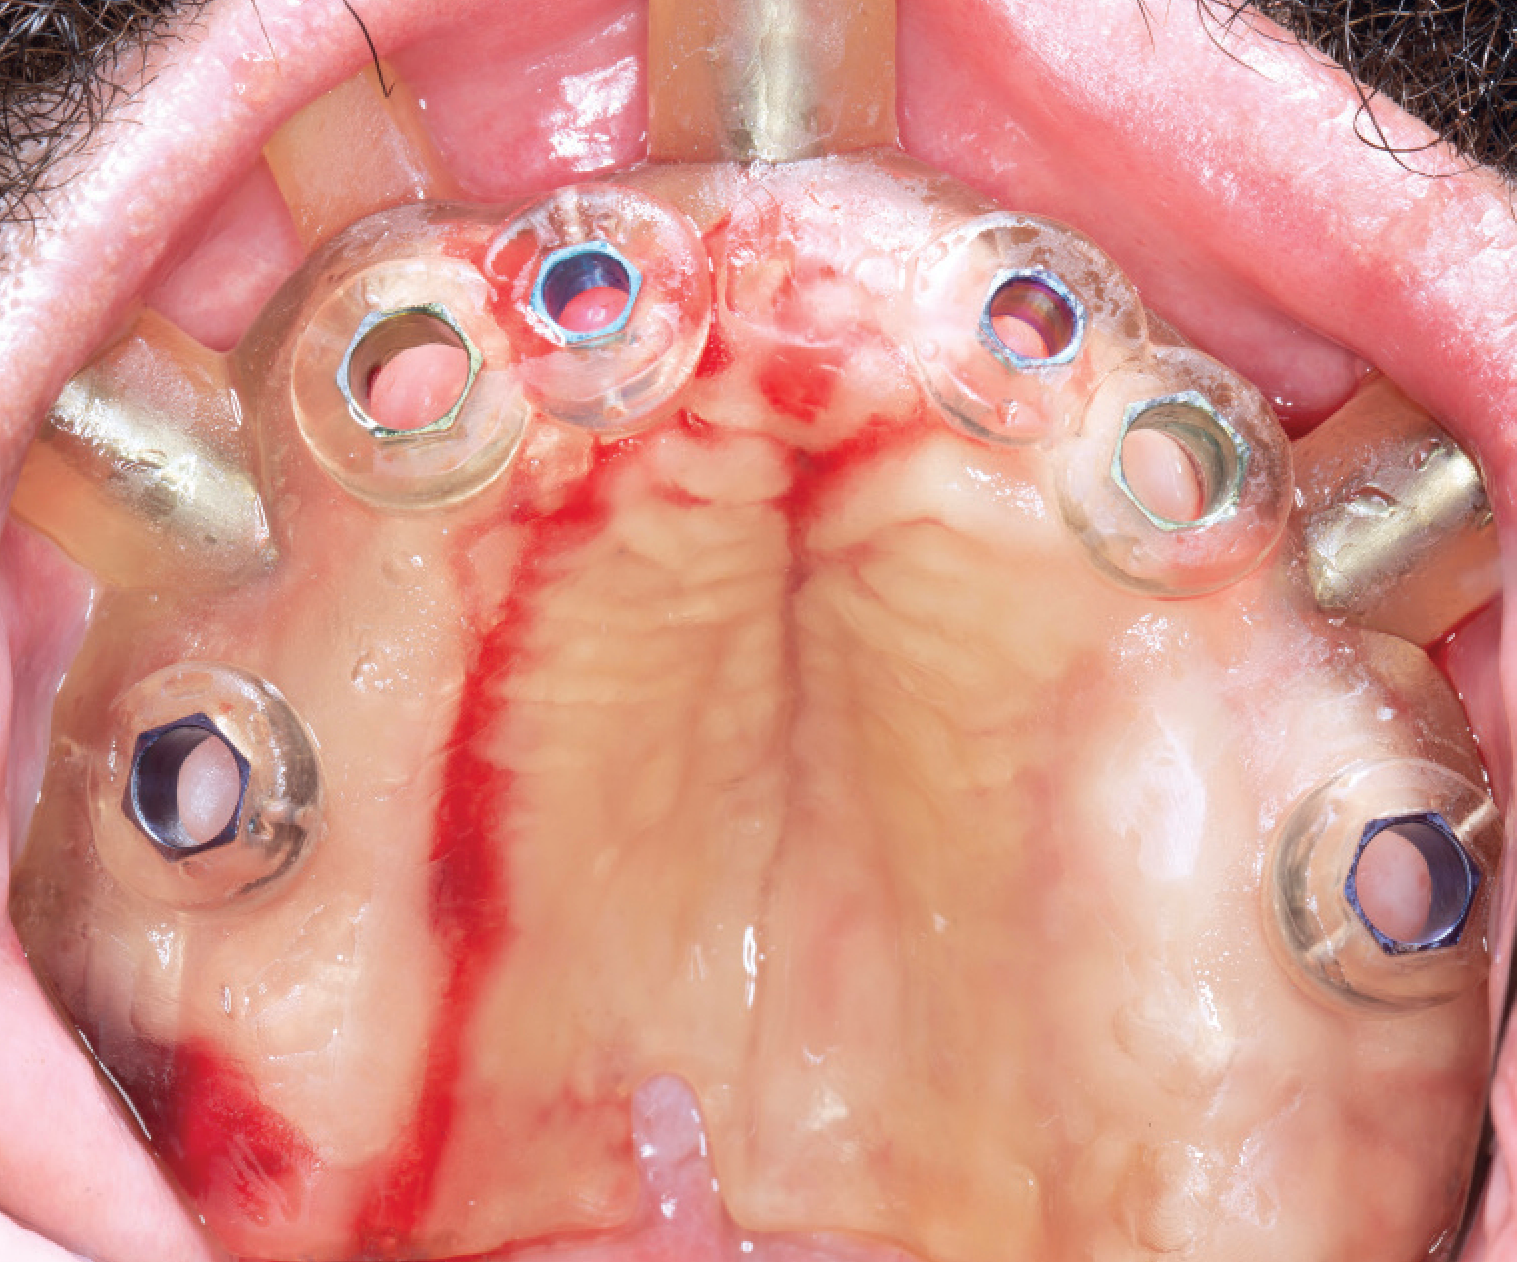

Guided Implant Placement

Computer-guided surgery using 3D imaging and surgical guides for precise implant positioning.

Guided Implant Placement - Surgical Guide

Guided Implant Placement - Final Result